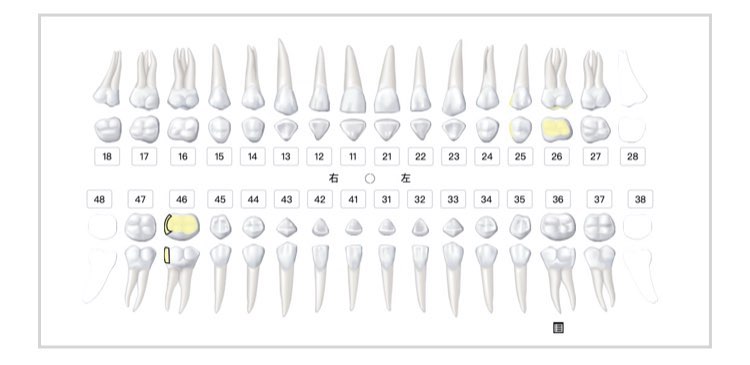

牙齿综合检查报告